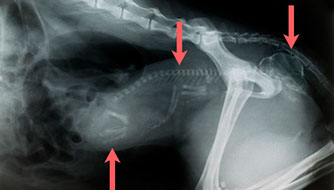

Schrotkugeln im Kopf eines Jagdhundes